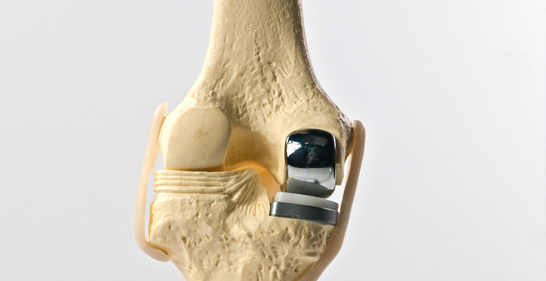

2. Partial Knee Replacement (PKR)

Icon Only the damaged portion of the knee is replaced.

Icon Preserves healthy bone and ligaments.

Icon Suitable for patients with localized arthritis in one knee compartment.